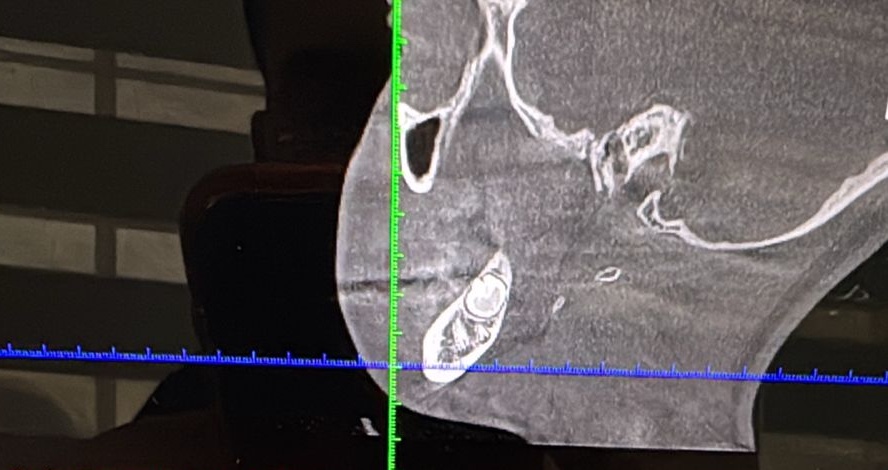

El padre Noel Ulloa, indico que su hija tiene la mandíbula rota, que requiere una cirugía y que ellos no cuentan con los recursos para costear los gastos.